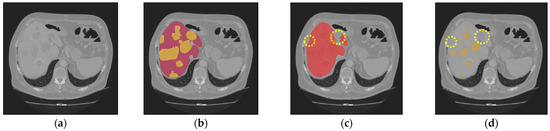

Objective: Segmentation of liver and liver tumors from 3D medical images is a challenging and computationally expensive task. Organs that are in close proximity may have similar shape, texture, and intensity, which makes it difficult for accurate segmentation. Accurate segmentation of liver tumors [...] Read more.

Objective: Segmentation of liver and liver tumors from 3D medical images is a challenging and computationally expensive task. Organs that are in close proximity may have similar shape, texture, and intensity, which makes it difficult for accurate segmentation. Accurate segmentation of liver tumors is important for diagnosis and treatment planning of liver cancer. Methods: A hybrid model with a U-Net based structure and the Whale Optimization Algorithm (WOA) was proposed. WOA was used to optimize the hyperparameters of the conventional LiTS-Res-UNet to obtain the best segmentation performance of the deep learning model. Results: The LiTS-Res-Unet + WOA hybrid model achieved a performance of 99.54% for accuracy, with a Dice coefficient of 92.38% and a Jaccard index of 86.73% on the benchmark dataset, outperforming state-of-the-art methods. Conclusions: The WOA-based adaptive search space was able to obtain an optimal set of hyperparameters for deep learning model convergence while increasing the accuracy of the model in the proposed hybrid model. The robust performance and clinical applicability of the model in liver tumor segmentation were demonstrated. Full article

Show Figures

Figure 1